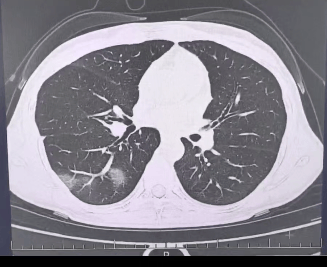

检查结果显示btc兑换,

程女士的好几叶肺

都出现了“白肺”现象btc兑换,

指间血氧饱和度只有 88%btc兑换,

血心肌酶谱、肌钙蛋白的指标、肝功能的指标

也出现了明显的异常btc兑换。

确诊流感(重型)btc兑换!

图源:杭州市第三人民医院微信公众号